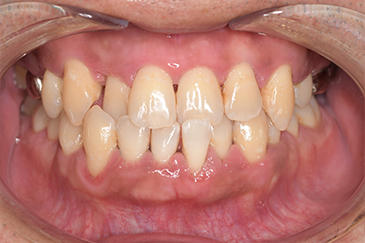

CASE 14

下顎before

下顎after

臼歯before

臼歯after

| 年齢・性別 | 27歳・男性 |

| 主訴 | 歯石とりたい |

| 治療内容 | スケーリング |

| 治療期間 | 30分 |

| 治療費 | 約1,500円(保険診療) |

| リスク・副作用 | 知覚過敏、歯肉退縮、出血 |

| 治療方針 | 歯列不正でプラークがつきやすいため、TBIを行い定期的に歯石を除去していきます。 プラークコントロールが出来るようになったら定期検診でクリーニングを行っていきます。 |